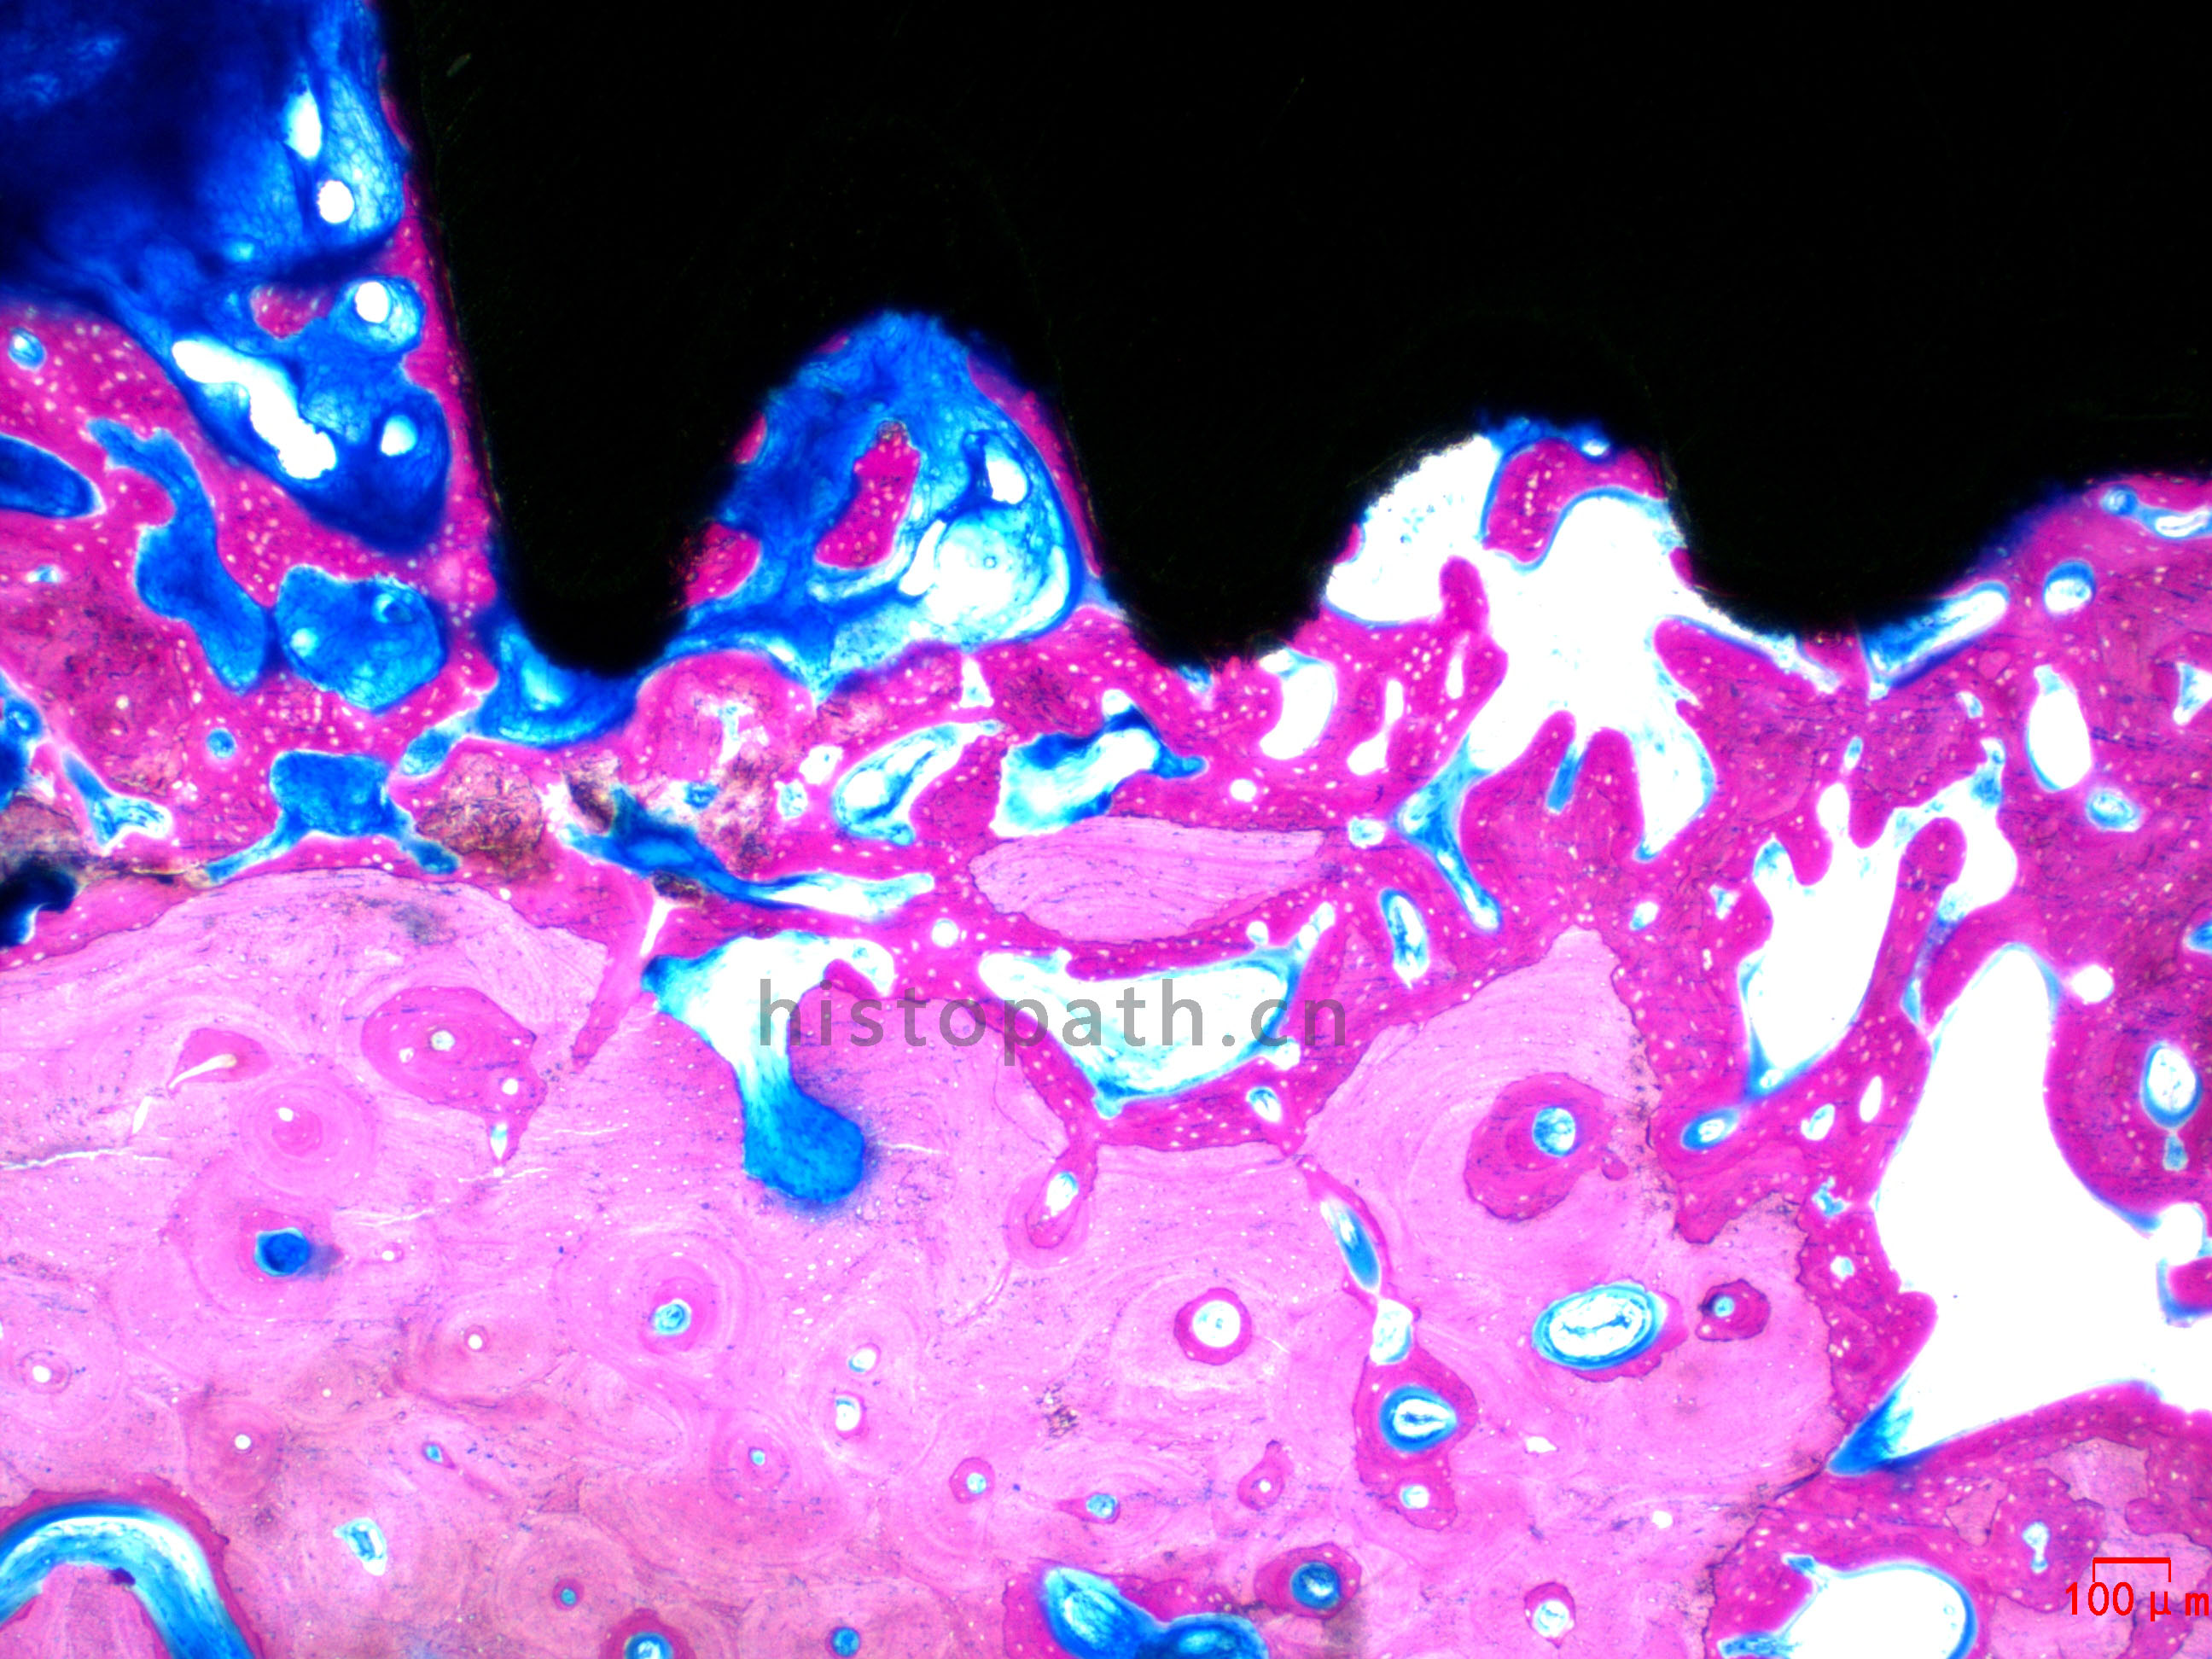

牙体种植:亚甲基蓝--酸性品红染色

针对不同的病理阅片指标需求,行HE染色、Masson染色、亚甲基蓝-酸性品红染色、VG染色、Movat染色等。